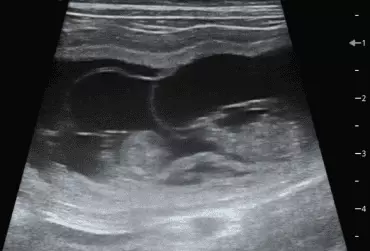

W literaturze opisano niewiele przypadków ciąż bliźniaczych jednokosmówkowych u suk. W trakcie wczesnej diagnostyki ultrasonograficznej ciąży u suki rasy whippet (chart angielski) zobrazowano pęcherz ciążowy, w którym znajdowały się dwa zarodki. Podczas badań kontrol­nych zarodki, a później płody wykazywały prawidłową organogenezę i żywotność. Ich rozwój przebiegał podobnie względem pozostałych ośmiu płodów. W 63. dniu ciąży wykonano zabieg cesarskiego cięcia i wydobyto dwa płody tej samej płci, o bardzo podobnym wyglądzie, z dwóch pęcherzy płodowych przyczepionych do jednego łożyska, oraz pozostałe osiem płodów.

Ryzyko związane z ciążą bliźniaczą jednokosmówkową u ciężarnych suk nadal jest nieznane, istnieją jednak doniesienia o śmierci płodu lub płodów w ciążach jednokosmówkowych u tego gatunku. Badanie ultrasonograficzne w czasie ciąży pozwala na wczesne rozpoznanie ciąży jednokosmówkowej, a monitorowanie żywotności płodów może ograniczyć ryzyko powikłań położniczych i przynieść korzyści zdrowotne zarówno samicy, jak i rodzeństwu z miotu.